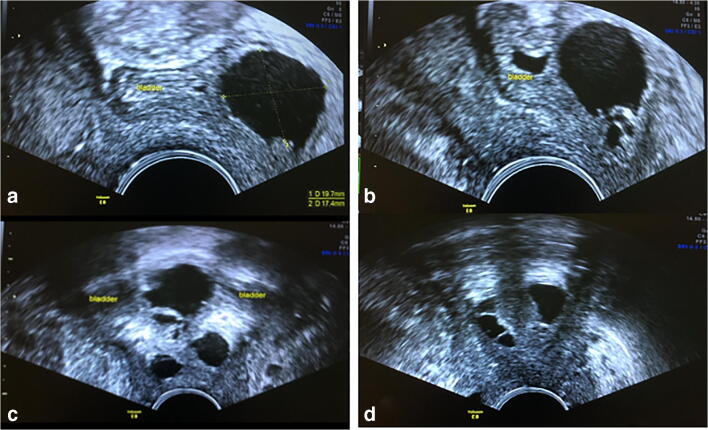

Fig. 1.

Transvaginal ultrasound showing cystic lesions (diverticulum) in the bladder wall and around the urethra. a Mid-sagittal image shows a cystic portion of the diverticulum in the bladder wall over the trigone. b Smaller cystic lesions inferior to the larger cystic structure are shown at the trigone. c Coronal images show multiple cystic lesions at the base of the bladder and along the proximal urethral length. The bladder is empty. d Coronal section showing cystic structures in the distal urethra